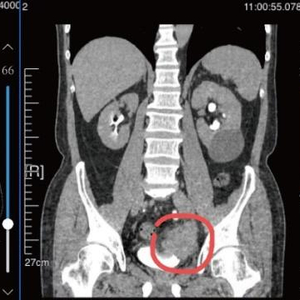

治疗前CT表现

多番辗转,老许来到瑞金医院北部院区泌尿外科就诊,邵远主任接诊了老许,并为他安排了CTU(泌尿系统造影)增强检查,结果显示,老许的膀胱左侧的肿块很大(56*47mm),且已经侵犯到膀胱之外的盆腔血管。

化疗+免疫治疗3个疗程后CT表现

几个月后,老许再次入院,进行CTU(泌尿系统造影)增强检查,结果显示:膀胱左侧壁憩室肿块大幅度缩小,范围约22*18mm,左侧输尿管未见明显积水扩张,左侧输尿管下段间断显影。